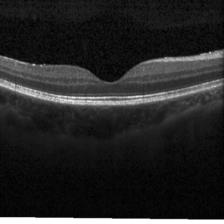

Retinal OCTClick any thumbnail to select it — images switch automatically when you change the model

CNV

DME

DRUSEN

NORMAL

4-class retinal OCT classification: CNV, DME, Drusen, Normal